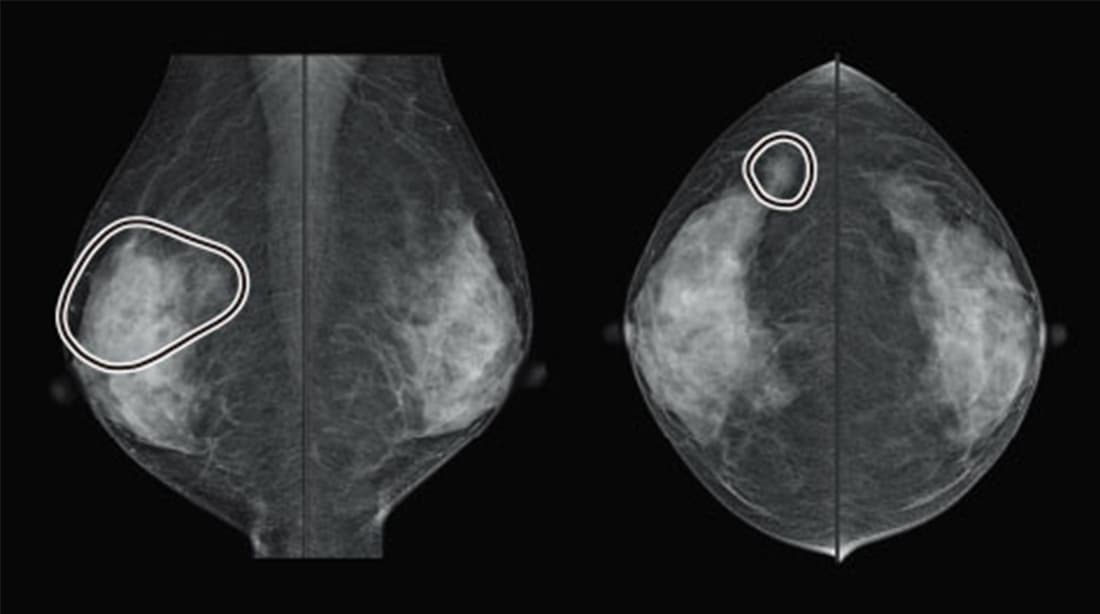

【症例3】 FAD

CADは左右の乳房を比較することで濃度の上昇を検出するアルゴリズムを搭載しています。症例3で、CCのCADマークは病変の可能性が高いFADを的確に指し示していますが、MLOにあるような偽陽性もみられます。CADの指摘を病変とみるのか、乳腺の重なりと読み解くかどうかの判断の際、読影医には高い読影力が求められます。